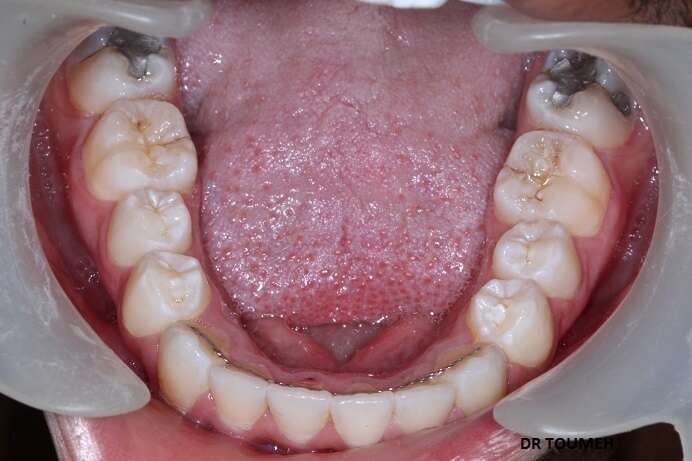

Avant

Après